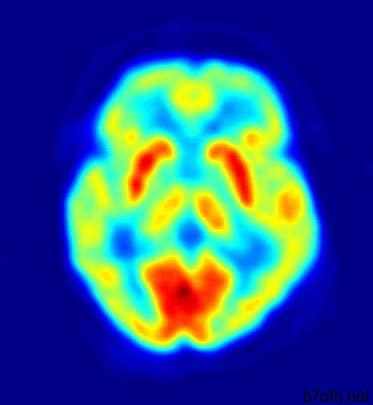

التصوير المقطعي للانبعاث البوزيتروني (PET) هو إجراء يعتمد على الكمبيوتر يتم فيه إدخال مركب إشعاعي محدد في المخ (أو أي جهاز آخر قيد الدراسة) ، ويتم تتبع سلوكه. في نهاية المطاف ، تنتج هذه المعلومات ، مع نمذجة الكمبيوتر ، صورة مستعرضة للعملية الفسيولوجية قيد الدراسة.